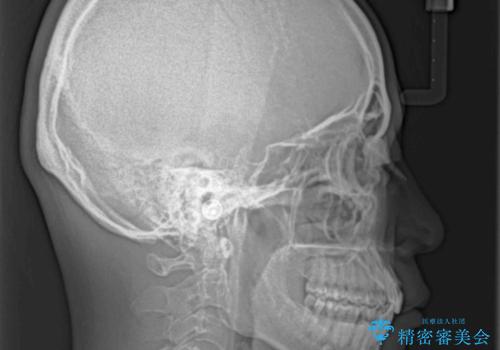

しっかりと装着時間を守り、ゴムかけも徹底していただいたので、思いの外口元を引っ込めることができました。

これ以上の改善を望まれましたが、非抜歯矯正でこれ以上口元を引っ込めると食いしばりすやすい咬合となるため、この歯列で終了としました。